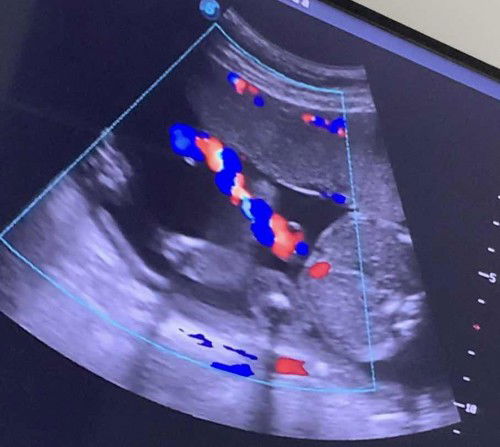

#pleasehelp Bun ada pengalaman ga waktu usg ari ari terpilin? Trus hal apa yg harus di lakuin? Btw ini usg ari2 terpilin di kehamilan 22w aku. Di kasi PR sama dokternya jgn capek sama jgn banyak gerak dlu. Padahal aku juga ga banyak aktivitas kok. Jd khawatir 😔